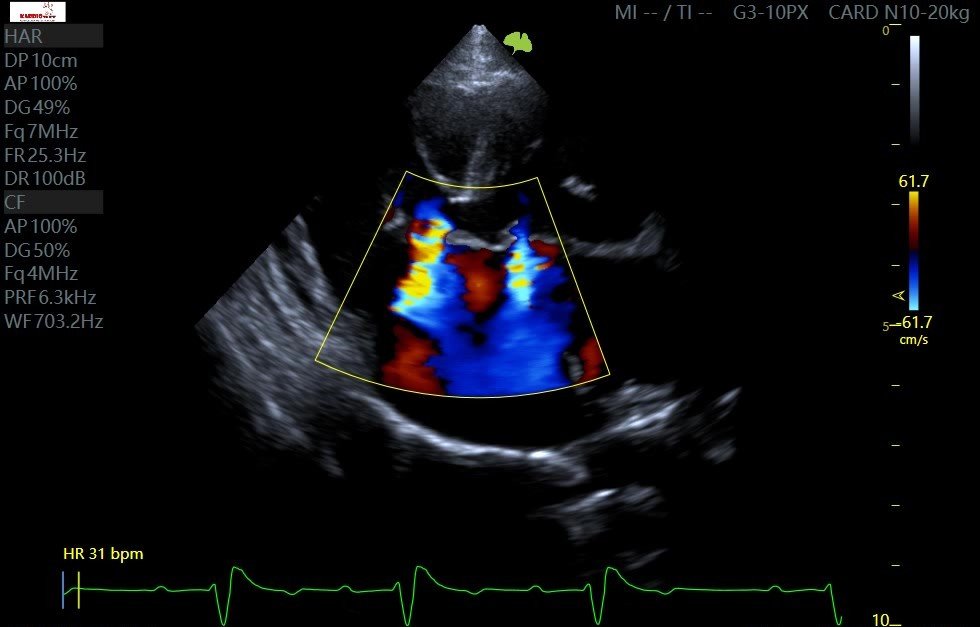

• Znacznej wielkości ubytek w przegrodzie międzyprzedsionkowej z przepływem:

• lewo-prawym w fazie rozkurczu

• prawo-lewym w fazie skurczu

• Wtórne znaczne powiększenie prawego przedsionka i prawej komory

• Spłaszczenie przegrody międzykomorowej z paradoksalnym jej ruchem oraz widoczny pseudoaneuryzm przegrody międzykomorowej w okolicy pod zastawką aortalną z możliwym przeciekiem lewo-prawym

• Dysplazja zastawki mitralnej (o mniejszym nasileniu), z niedomykalnością

Na podstawie całości obrazu rozpoznano: Częściowy kanał przedsionkowo-komorowy (PAVC).

PAVC -Color Flow Doppler